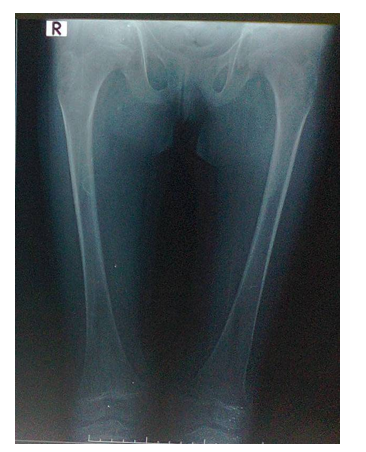

The younger sister laboratory tests performed during May, 2023 showed normal serum calcium of 9 mg/dL and normal serum phosphorus of 5.16 mg/dL. However, the alkaline phosphatase was high at 164 u/l (Normally less than 140 u/l). Old radiographs of the older sister showed osteopenia, fracture in the upper limb, and progressive bowing with no rachitic changes. Figure-2A and B shows a lower limb radiographs taken during December, 2019. Later radiographs showed more severe bowing (Figure-2C).

Figure-2A: A lower limb radiograph taken during December, 2019

Figure-2B: A lower limb radiograph taken during December, 2019